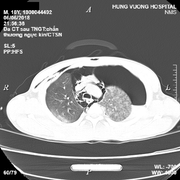

Chàng thanh niên 18 tuổi nguy kịch sau tai nạn giao thông, tràn khí màng phổi nặng, tràn khí dưới da vùng mặt cổ, gãy xương đòn phải, gãy đa xương sườn.